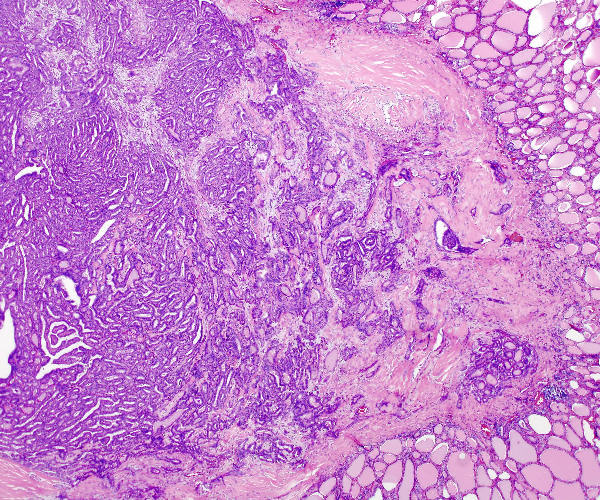

Thyroid papillary carcinoma

Thyroid_papillary_carcinoma_histopatholgy_(1)